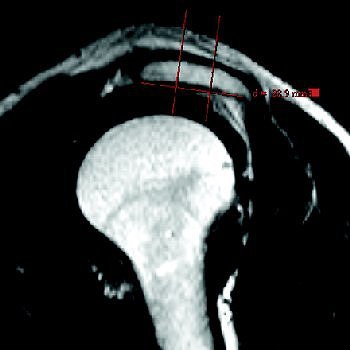

![]() |

| Mathematic determination of acromial shape. Then on parasagittal T2-weighted MR image, angle between anterior third and posterior two-thirds is measured. In this case, the anterior angle of deflection is 180° - 168° = 12°, indicating slightly curved (type 2) acromion in S-2 position. |